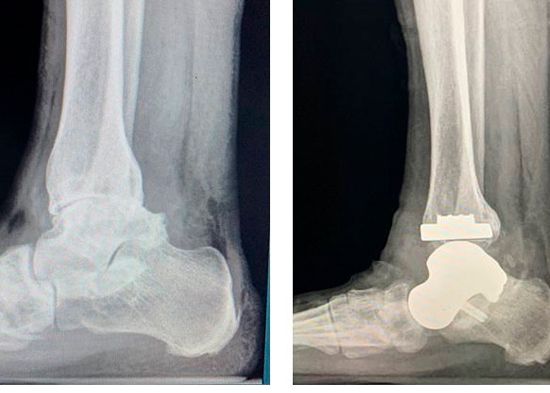

Aprobado por la Administración de Drogas y Alimentos de los EE.UU. (FDA) el “Patient-Specific Talus Spacer” es el implante impreso en 3D que se utiliza para reemplazar el astrágalo enfermo, el hueso en la articulación inferior del tobillo que conecta la pierna con el pie. El implante de astrágalo se fabrica para las especificaciones de cada paciente usando imágenes por tomografía computarizada (CT) del tobillo saludable del paciente, el cual se reversa y se utiliza para imprimir la nueva articulación en tres tamaños distintos para determinar el mejor tamaño para el producto final. Una vez que el Dr. Chapman determina el mejor tamaño para el paciente, la articulación de reemplazo es impresa de metal, como titanio. El astrágalo enfermo del paciente es removido y reemplazado con el implante personalizado durante la cirugía.